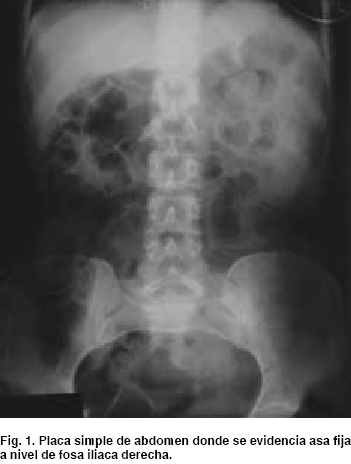

En la placa simple de abdomen se evidencia asa fija a nivel de fosa iliaca derecha y nivel hidroaéreo a este nivel (Figura 1). En el rastreo sonográfico abdominal, se evidencia líquido libre en cavidad a nivel de fosa iliaca derecha.